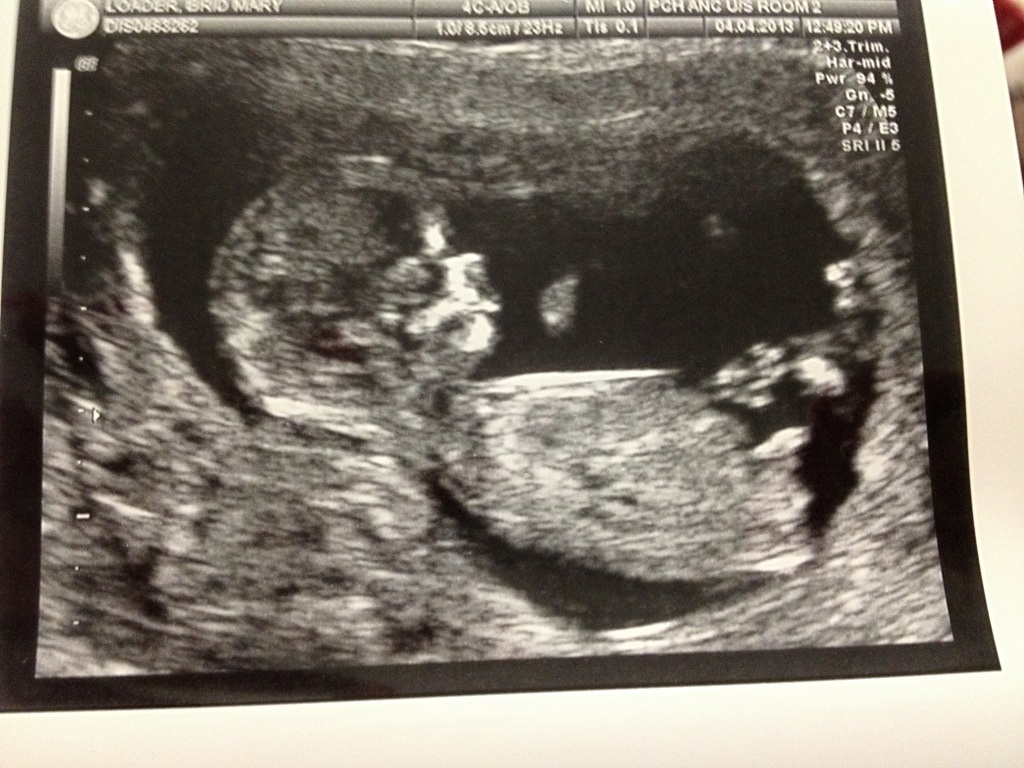

Hi ladies these are my shots at 12+ 6 ..l convinced boy even though all my preg is like it was with DD Attachment 10618